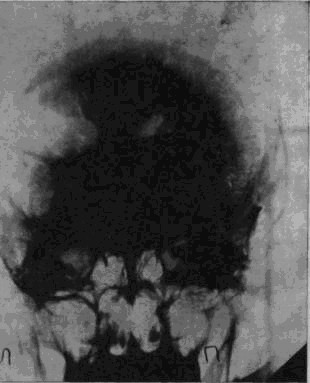

Рис. 1а. Рентгеновский снимок черепа больного Засецкого после введения воздуха в желудочки мозга (пнеймоэнцефалограмма). На нем можно видеть резко расширенный левый боковой желудочек и скопление воздуха в подоболочечных пространствах мозга теменно-затылочной области левого полушария

Осколок внедрился в вещество задних, теменно-затылочных отделов мозга и разрушил мозговую ткань этой области.

Ранение осложнилось воспалительным процессом; он не распространенный, местный, ограничен лишь областями мозга, примыкающими к непосредственному месту ранения, но теменно-затылочные отделы левого полушария, отделы, так тесно связанные с анализом пространственного мира, необратимо повреждены, и уже начинается процесс образования рубцов, который неизбежно повлечет за собою частичную атрофию расположенных вблизи ранения участков мозгового вещества.

Рис. 16. Черное пятно в правом полушарии – осколок, расположенный под кожей от поверхностного шрапнельного ранения, полученного им за год до основного ранения

И через десять лет после ранения – еще одна выписка из истории болезни, на этот раз сделанная на основе рентгенограммы.

В спинномозговой канал введен воздух. Он поднялся вверх, заполнил контуры желудочков мозга и те пустоты, которые образовались в результате сморщивания вещества отделов мозга, непосредственно примыкающих к месту ранения. «Процесс рубцевания вызвал атрофические изменения в левом боковом желудочке. Стенки его подтянуты к поверхности мозга, подоболочечные пространства резко расширены. Значительный местный атрофический процесс».

Ранение вызвало местную атрофию мозгового вещества левой теменно-затылочной области.